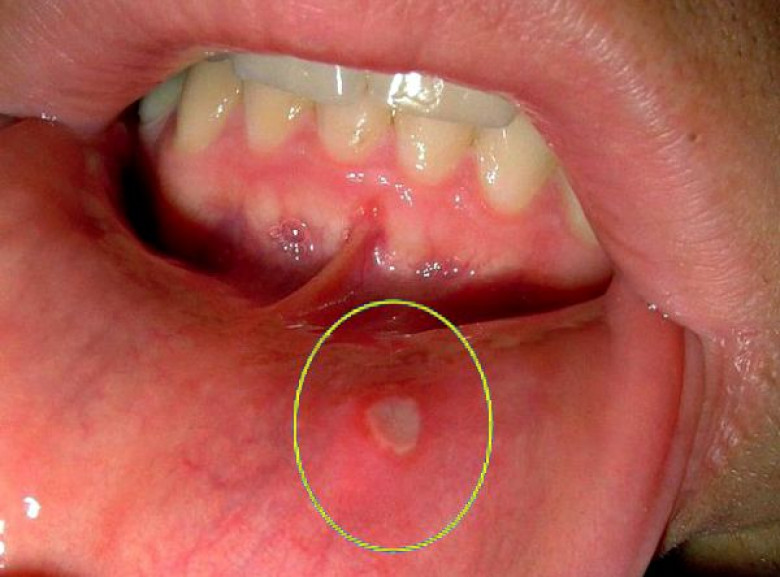

Բերանի խոռոչի թեթև կարմրությունը հանդիսանում է ստոմատիտի առաջին նախանշանը: Ժամանակի ընթացքում ավելի ուռում ու այտուցվում են: Եթե չսկսել այս շրջանում բուժումը, կարմրությունը կփոխարինվի խոցոտումներով՝ ոչ մեծ չափերի, օվալ կամ կլոր ձևով, մոխրագույն կամ սպիտակ գույնով, կարմիր երիզով և պատված թաղանթով: Եվ շուրջը գտնվող հյուսվածքը բացարձակապես առողջ է: Լեզուն նույնպես շատ ցավոտ է, և դժվարացնում է սննդի ընդունումը:

Խոցերը հիմնականում առաջանում են եզակի՝ սա թեթև ձևն է: Կա նաև բարդացած ձև, երբ մի քանի խոցեր՝ տարբեր ձևի և չափերի միավորվում են: Խոցերի առաջացումը զուգորդվում է ջերմության բարձրացմամբ, ավշային հանգույցների բորբոքմամբ, ինքնազգացողության վատացմամբ, գլխացավով, ախորժակի կորուստով, փորկապությամբ և այլ ախտանիշներով:

Աֆթոզ ստոմատիտ-Պատճառ կարող են հանդիսանալ ՍԱՀ-ի հիվանդությունները, ալերգիկ ռեակցիաները, վիրուսները, ռևմատիզմը, ժառանգականությունը: Բերանի խոռոչում հայտնվում են 3-5 մմ խոցեր մոխրասպիտակավուն գունավորմամբ, միայնակ կամ բազմակի, վատ ինքնազգացողություն, ջերմության բարձրացում և ցավեր խոցոտված հատվածներում: Կարող է լինել սուր և անցնել խրոնիկական ռեցիդիվող ստոմատիտի: